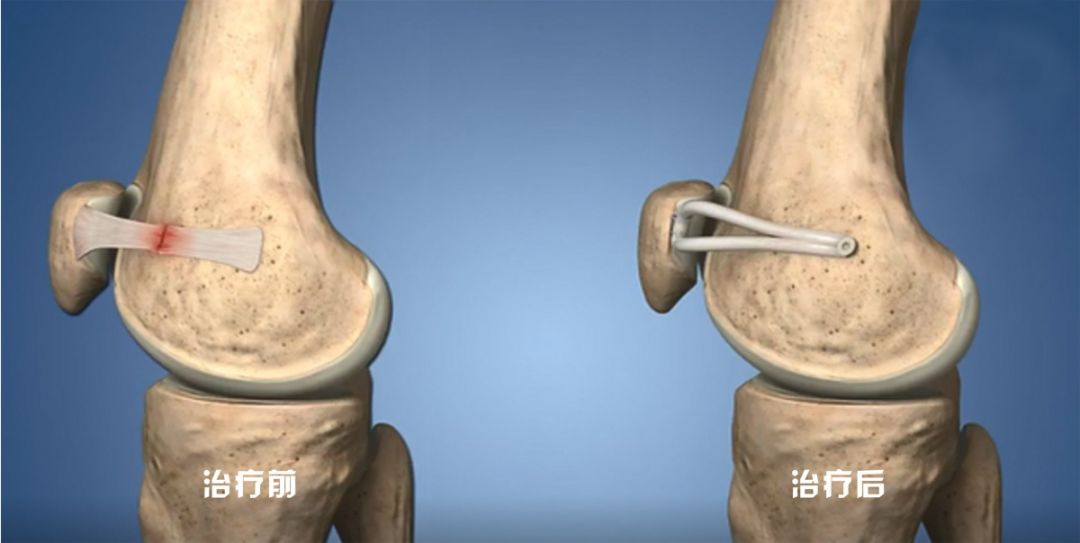

最后,手术团队在汤女士髌骨内缘做一个3~4cm切口,将取出的自体半腱肌腱移植,替换原本断裂了的内侧髌股韧带,重建髌骨内侧支持结构。

治疗前后示意图

医生介绍,在移植肌腱最终固定前,需要确定移植肌腱的合适张力:“张力如果太小,限制髌骨外移的作用有限,术后仍会存在髌骨不稳;而张力如果太大,又会影响屈伸膝关节过程中髌骨在股骨滑车上的滑移,从而导致膝关节屈伸受限。”

因此,确保移植肌腱最终的合适张力是手术的难点。术中,团队首先拉紧移植的肌腱,向髌骨施加应力,一点点调节其被动滑动距离,并再次通过关节镜检确认屈伸膝过程中髌骨在合适的轨迹活动后,最后才用螺钉固定,为汤女士移植肌腱设置了合适张力。